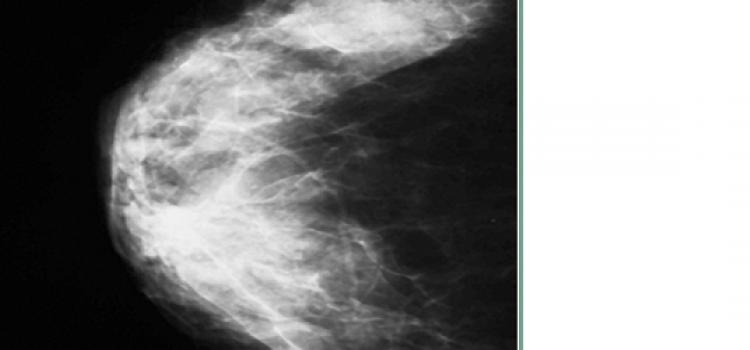

Mammography is one of the great triumphs of innovation in breast cancer care, as it is the only screening technology ...